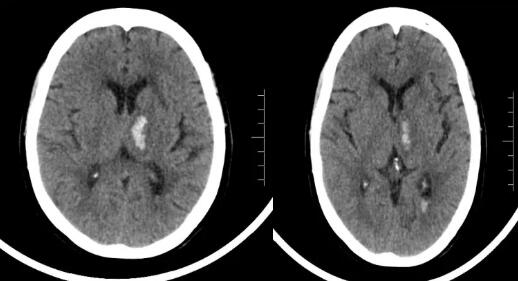

综合种种迹象,阿青和爸爸都以为妈妈精神出了状况,急忙带着她前往中山某医院做检查。外院医生立即为她做了相关检查,影像资料显示阿青妈妈左侧丘脑出血,高血压病3级。治疗后,效果并不明显。阿青急忙又陪妈妈来到广东三九脑科医院。

我院副院长,神经内科专家王展航接诊了患者。结合外院相关资料及追问病史,诊断患者为高血压脑出血。

影像资料显示异常

明确病因后,王展航立即为患者制定了针对性的治疗方案和康复疗程。好在患者出血量小,经过积极治疗后,现在她不仅能认得出阿青,并能对答如流。